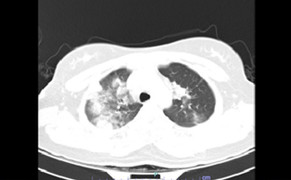

Tiến sĩ Hamiduzzaman cho biết chẩn đoán viêm phổi sẽ yêu cầu chụp X-quang phổi để xem sự bất thường trong phổi, nơi xuất hiện bệnh viêm phổi.